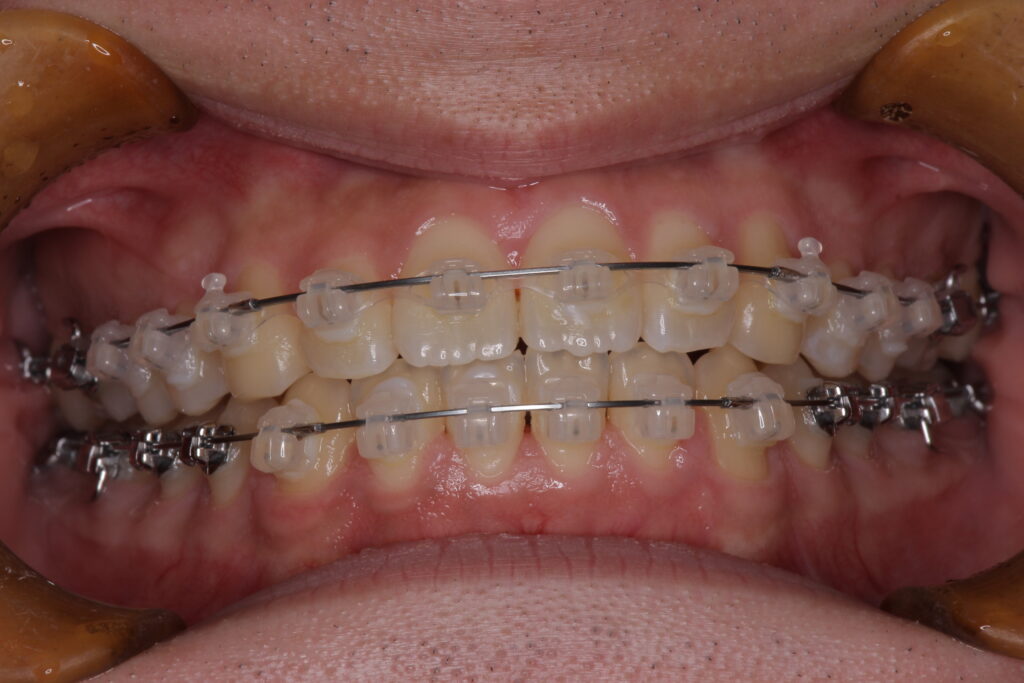

本格的な矯正治療とはマルチブラケットと呼ばれるブラケット+ワイヤーを用いた方法やマウスピース型の装置を使用する方法などがありますが、大人の歯(永久歯)を積極的に動かすことでかみ合わせの能力を高めることを目的としています。

参考症例:受け口を一期治療で治療したケース(7歳で開始し、8ヶ月の一期治療を実施)